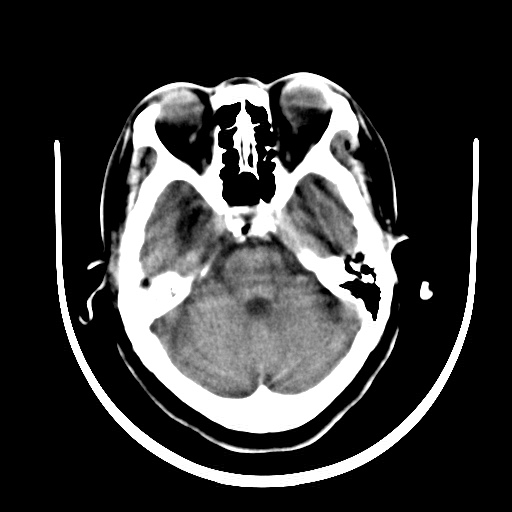

标题: CT16579:女 65岁间断性抽搐. [打印本页]

标题: CT16579:女 65岁间断性抽搐.

考虑右侧颞叶脑软化灶并脑穿通畸形;建议必要时行进一步检查。

右侧蛛网膜囊肿

右颞叶脑软化灶。余未见明显异常。

考虑右颞叶脑软化灶

右颞叶软化灶,右基底节区腔隙性脑梗塞;